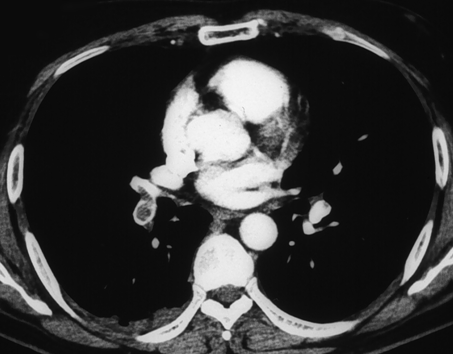

呼吸不全症例(急性肺塞栓症)の胸部造影CT画像

肺動脈に血栓塞栓を認めた。